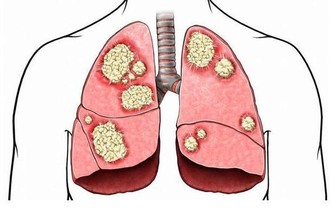

人為什麼會做春夢、被鬼壓床? 這8 種夢或是疾病信號

當然,必須強調的是,這張圖目前主要是根據醫生經驗判斷得出的,疾病導致了某某夢境,僅僅是有可能性,並不一定準確。